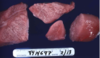

Describe morphological problem

Muscle is pale, swollen and dry to the touch